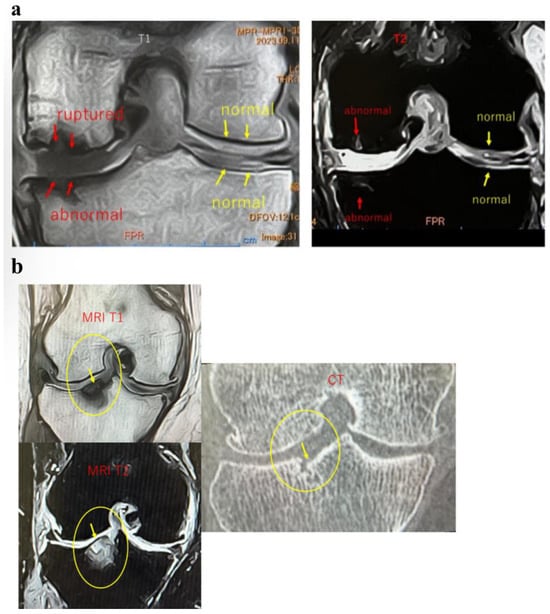

BMLs are a critical pathology reflecting early structural changes in the progression of knee OA. They are not merely bone marrow edema signals but are closely tied to subchondral bone structural failure and irreversible joint surface deformity, as demonstrated by pathological and imaging studies [15,16]. Subchondral bone plate (SBP) tear is considered a severe lesion indicating loss of subchondral bone support, directly contributing to cartilage damage and worsening pain. Additionally, joint surface collapse is associated with progressive changes, such as loss of load distribution capacity, trabecular remodeling, and bone sclerosis, serving as a key indicator of treatment response and long-term prognosis [1,17]. Comprehensive evaluation of these structural features allows for a more accurate understanding of BML severity and pathological diversity, contributing to the development of individualized treatment strategies. Aso et al. [3] reported that BMLs with SBP tear exhibit significantly increased inflammatory cell infiltration, fibroblast proliferation, angiogenesis, osteoclast activity, and abnormal cartilage formation, leading to elevated OABSs (Figure 1a,b).

Figure 1.

Histological evaluation of (a) subchondral bone plate (SBP) tear and (b) bone marrow lesion (BML) at the SBP-tear site (provided by K. Aso). (a) Representative histological images stained with hematoxylin and eosin (HE) are presented. In the SBP-intact sample (left), the SBP beneath the cartilage remains continuous, exhibiting a smooth and well-defined structure. In contrast, in the SBP-tear sample (right), the continuity of the SBP is clearly interrupted, as indicated by the yellow arrow, with evident structural breakdown and tear. SBP, subchondral bone plate. (b) HE-stained histological sections from the SBP-disrupted (+) site are presented. As indicated by the yellow arrow, the continuity of the SBP is clearly interrupted. Pathological alterations are evident within the bone marrow region, and high-magnification images reveal neovascularization (upper right), infiltration of inflammatory cells (lower right), and proliferation of fibroblasts (lower left). These findings suggest the progression of bone remodeling, inflammatory responses, and reparative fibrosis at the site of SBP tear. SBP, subchondral bone plate; HE, hematoxylin and eosin.

These findings indicate that SBP tear plays a decisive role in BML severity and pain mechanisms, suggesting its importance as a pathological marker in designing knee OA treatment strategies based on BMLs. Consequently, in our conservative treatment strategies targeting subchondral bone, we have prioritized the presence or absence of SBP tear and joint surface collapse (Figure 2a,b and Figure 3a,b).

Figure 2.

Imaging findings of normal and ruptured subchondral bone plate (SBP-tear). (a) Magnetic resonance imaging (MRI) findings of normal and ruptured subchondral bone plate (SBP-tear). Coronal sections of the knee joint are shown on T1-weighted (left) and T2-weighted (right) images. The SBP appears as a low-signal band, similar to cortical bone. The normal SBP, indicated by yellow arrows, demonstrates preserved continuity and a smooth contour. In contrast, the areas marked with red arrows show apparent disruption and irregularity of the SBP. Notably, on T2-weighted images, the presence of joint fluid signal extending into the marrow cavity suggests SBP disruption. (b) Evaluation of SBP disruption using MRI and computed tomography (CT). The left upper panel shows a T1-weighted MRI image, the left lower panel shows a T2-weighted MRI image, and the right panel presents a coronal CT image. In the MRI images, the areas indicated by yellow arrows demonstrate a clear loss of SBP continuity (SBP-tear). On T2-weighted images, the disruption is more distinctly visualized owing to the contrast with joint fluid signals. When the detection of SBP tear is challenging on MRI, CT imaging can provide clearer visualization of the cortical tear in the SBP.